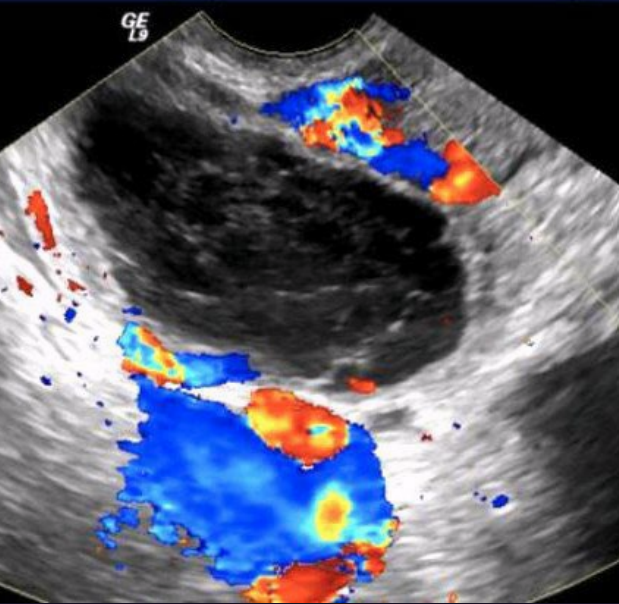

What type of fibroid is depicted in this image?

A. Intramural

B. Submucosal

C. Subserosal

D. Pedunculated

Intramural